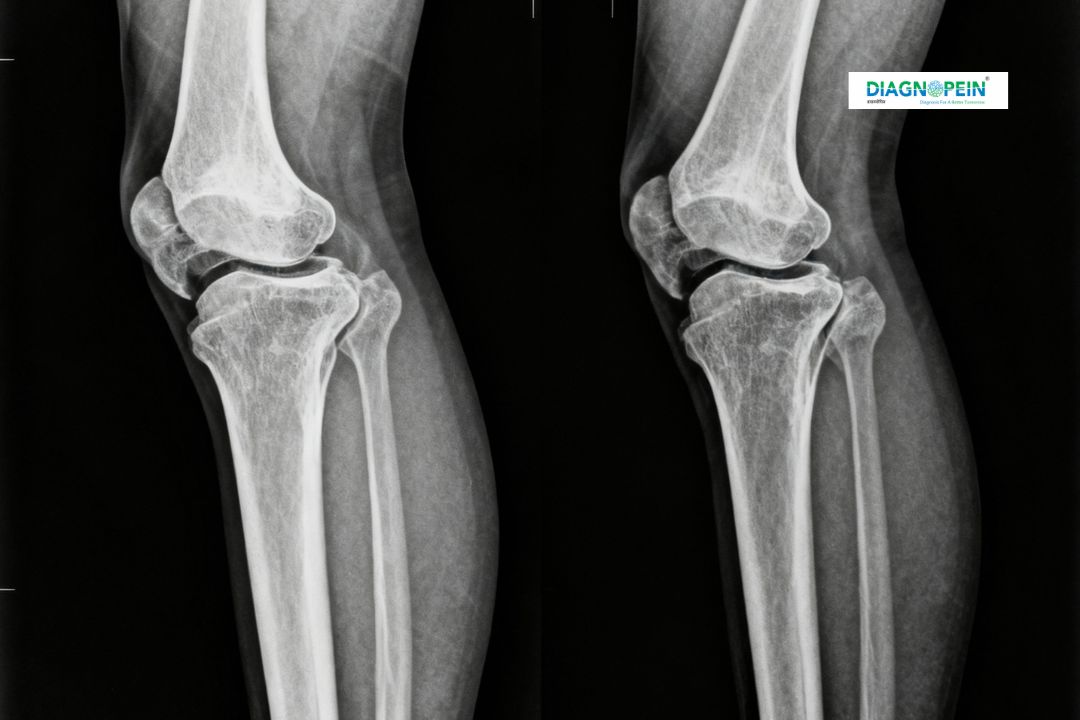

At Diagnopein Diagnostic Center in karad, our advanced X-Ray Both Knee Standing/Lateral/Skyline 2 View is a crucial imaging study used to evaluate knee joint structure, alignment, and bone health. This specialized test helps doctors assess weight-bearing conditions, joint spacing, and patellar positioning with high accuracy. Whether you are experiencing chronic knee pain, stiffness, post-injury symptoms, or degenerative changes, this X-ray study provides clear images to aid accurate diagnosis and effective treatment planning.

The procedure uses low-dose radiation technology, ensuring patient safety while producing clear digital images of both knees from multiple angles. These views—Standing, Lateral, and Skyline—help orthopedic specialists understand how the knees function under pressure during normal activities.

An X-Ray Both Knee Standing/Lateral/Skyline 2 View test is typically recommended when a patient complains of knee pain, arthritis symptoms, or joint instability. The Standing view helps analyze the alignment between the femur and tibia during weight-bearing, while the Lateral view helps visualize soft tissues, cartilage spaces, and joint effusions. The Skyline (axial) view provides an image of the patella (kneecap) and its articulation with the femur.

1. Joint space width and symmetry

2. Bone density and alignment

3. Patellofemoral angle and patellar height

4. Osteophyte (bone spur) presence

5. Soft tissue swelling or effusion